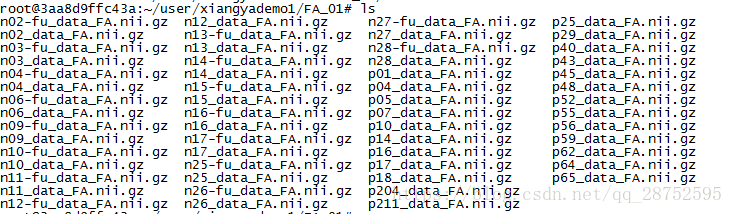

将4D FA数据和骨架加载到FSLView中:

cd stats fslview_deprecated all_FA -b 0,0.8 mean_FA_skeleton -b 0.2,0.8 -l Green